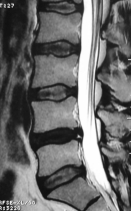

Eski Lomber Stabilizasyon Sistemi Altında Kırık (2)